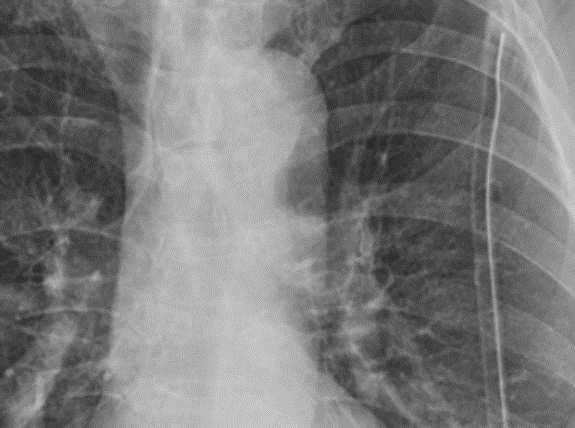

▲术后影像学